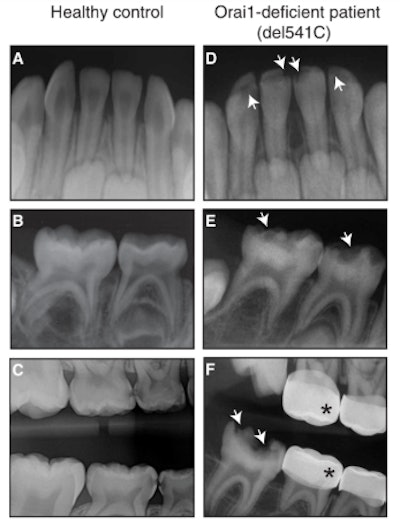

Lacruz and colleagues began their research by analyzing images of a dental patient with severe enamel defects. When the patient was 8 months old, he presented with "enamel hypoplasia of the primary mandibular central incisors and hypomineralization of primary maxillary incisors," the authors noted.

The condition of the patient's teeth continued to deteriorate over time. At around 6 years old, he presented with hypoplasia of the primary molars, severe caries, and multiple dental abscesses. Two years later, he had permanent molar incisor hypomineralization and posteruptive breakdown.

The patient underwent a bone marrow transplant and chemotherapy to treat his combined immunodeficiency, the authors reported. They did not, however, think the enamel defects stemmed from this treatment because the defects appeared in radiographs before the transplant and chemotherapy.